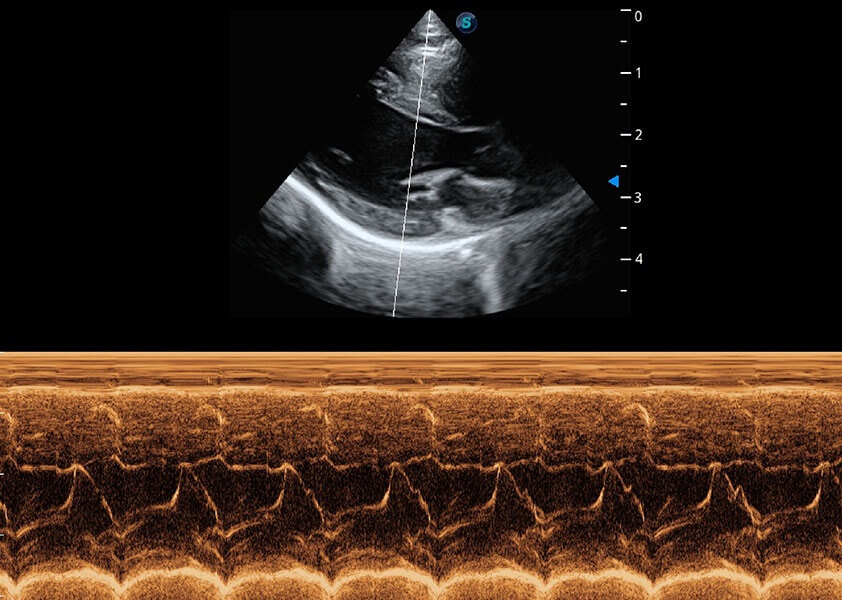

ProPet 60 作为一款高端台式动物超声设备,为动物医生的日常诊断提供了一系列贴合动物临床需求、解决临床实际问题的高级成像功能。凭借全系列高清探头,满足医生对腹部、心脏、生殖、浅表、肌骨等成像的所有需求,切实帮助您提升检查效率,提高诊断信心。

动物是人类最亲密的朋友和最值得信赖的伙伴。银河集团官网也一直致力于探索动物专用的超声影像解决方案。 全新推出的ProPet系列,是银河集团官网在动物超声影像智能化、专业化、精准化的一次跨越式革新。动物不能用言语来表述自己的不适,通过超声影像,ProPet系列搭建了动物医生与不同物种沟通的“桥梁”,为动物医生注入了“治愈之力”。